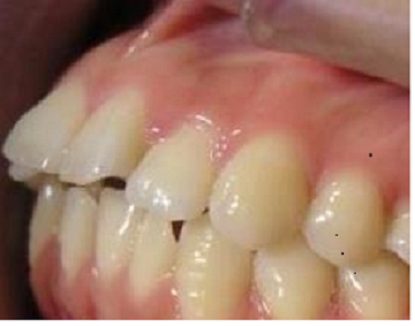

前牙深覆盖

前牙深覆盖就是人们平常所说的龅牙,上前牙相对下牙而言向前伸出过长与突出,前牙深覆盖是临床上比较常见的错颌畸形的一种,需要做牙齿矫正。